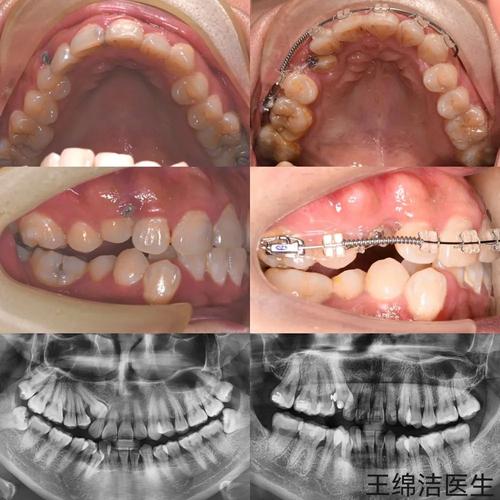

方案设计阶段(1-2周):基于检查数据,MDT团队会制定1-2套治疗方案,向患者详细说明不同方案的优缺点、治疗周期(通常1.5-3年)、费用及预期效果,对于牙齿拥挤不严重的患者,可选择隐形矫治器(如隐适美、时代天使),兼顾美观与便捷;对于需要显著改善咬合或骨性问题的患者,可能传统金属托槽或自锁托槽,配合微种植体支抗增强控制力,方案确定后,数字化系统会生成3D动画演示牙齿移动过程,患者确认后即可进入矫治器制作阶段。

矫治实施阶段(1-3年):传统托槽矫治通常需1-2小时完成粘接,隐形矫治器则需1周左右等待定制牙套交付,治疗期间,患者需定期复诊(传统托槽4-6周一次,隐形4-6周一次),医生会检查牙齿移动情况、调整矫治力,必要时更换弓丝或牙套,期间需特别注意口腔卫生,使用正畸专用牙刷、牙线、冲牙器清洁托槽周围,避免龋坏和牙周炎。